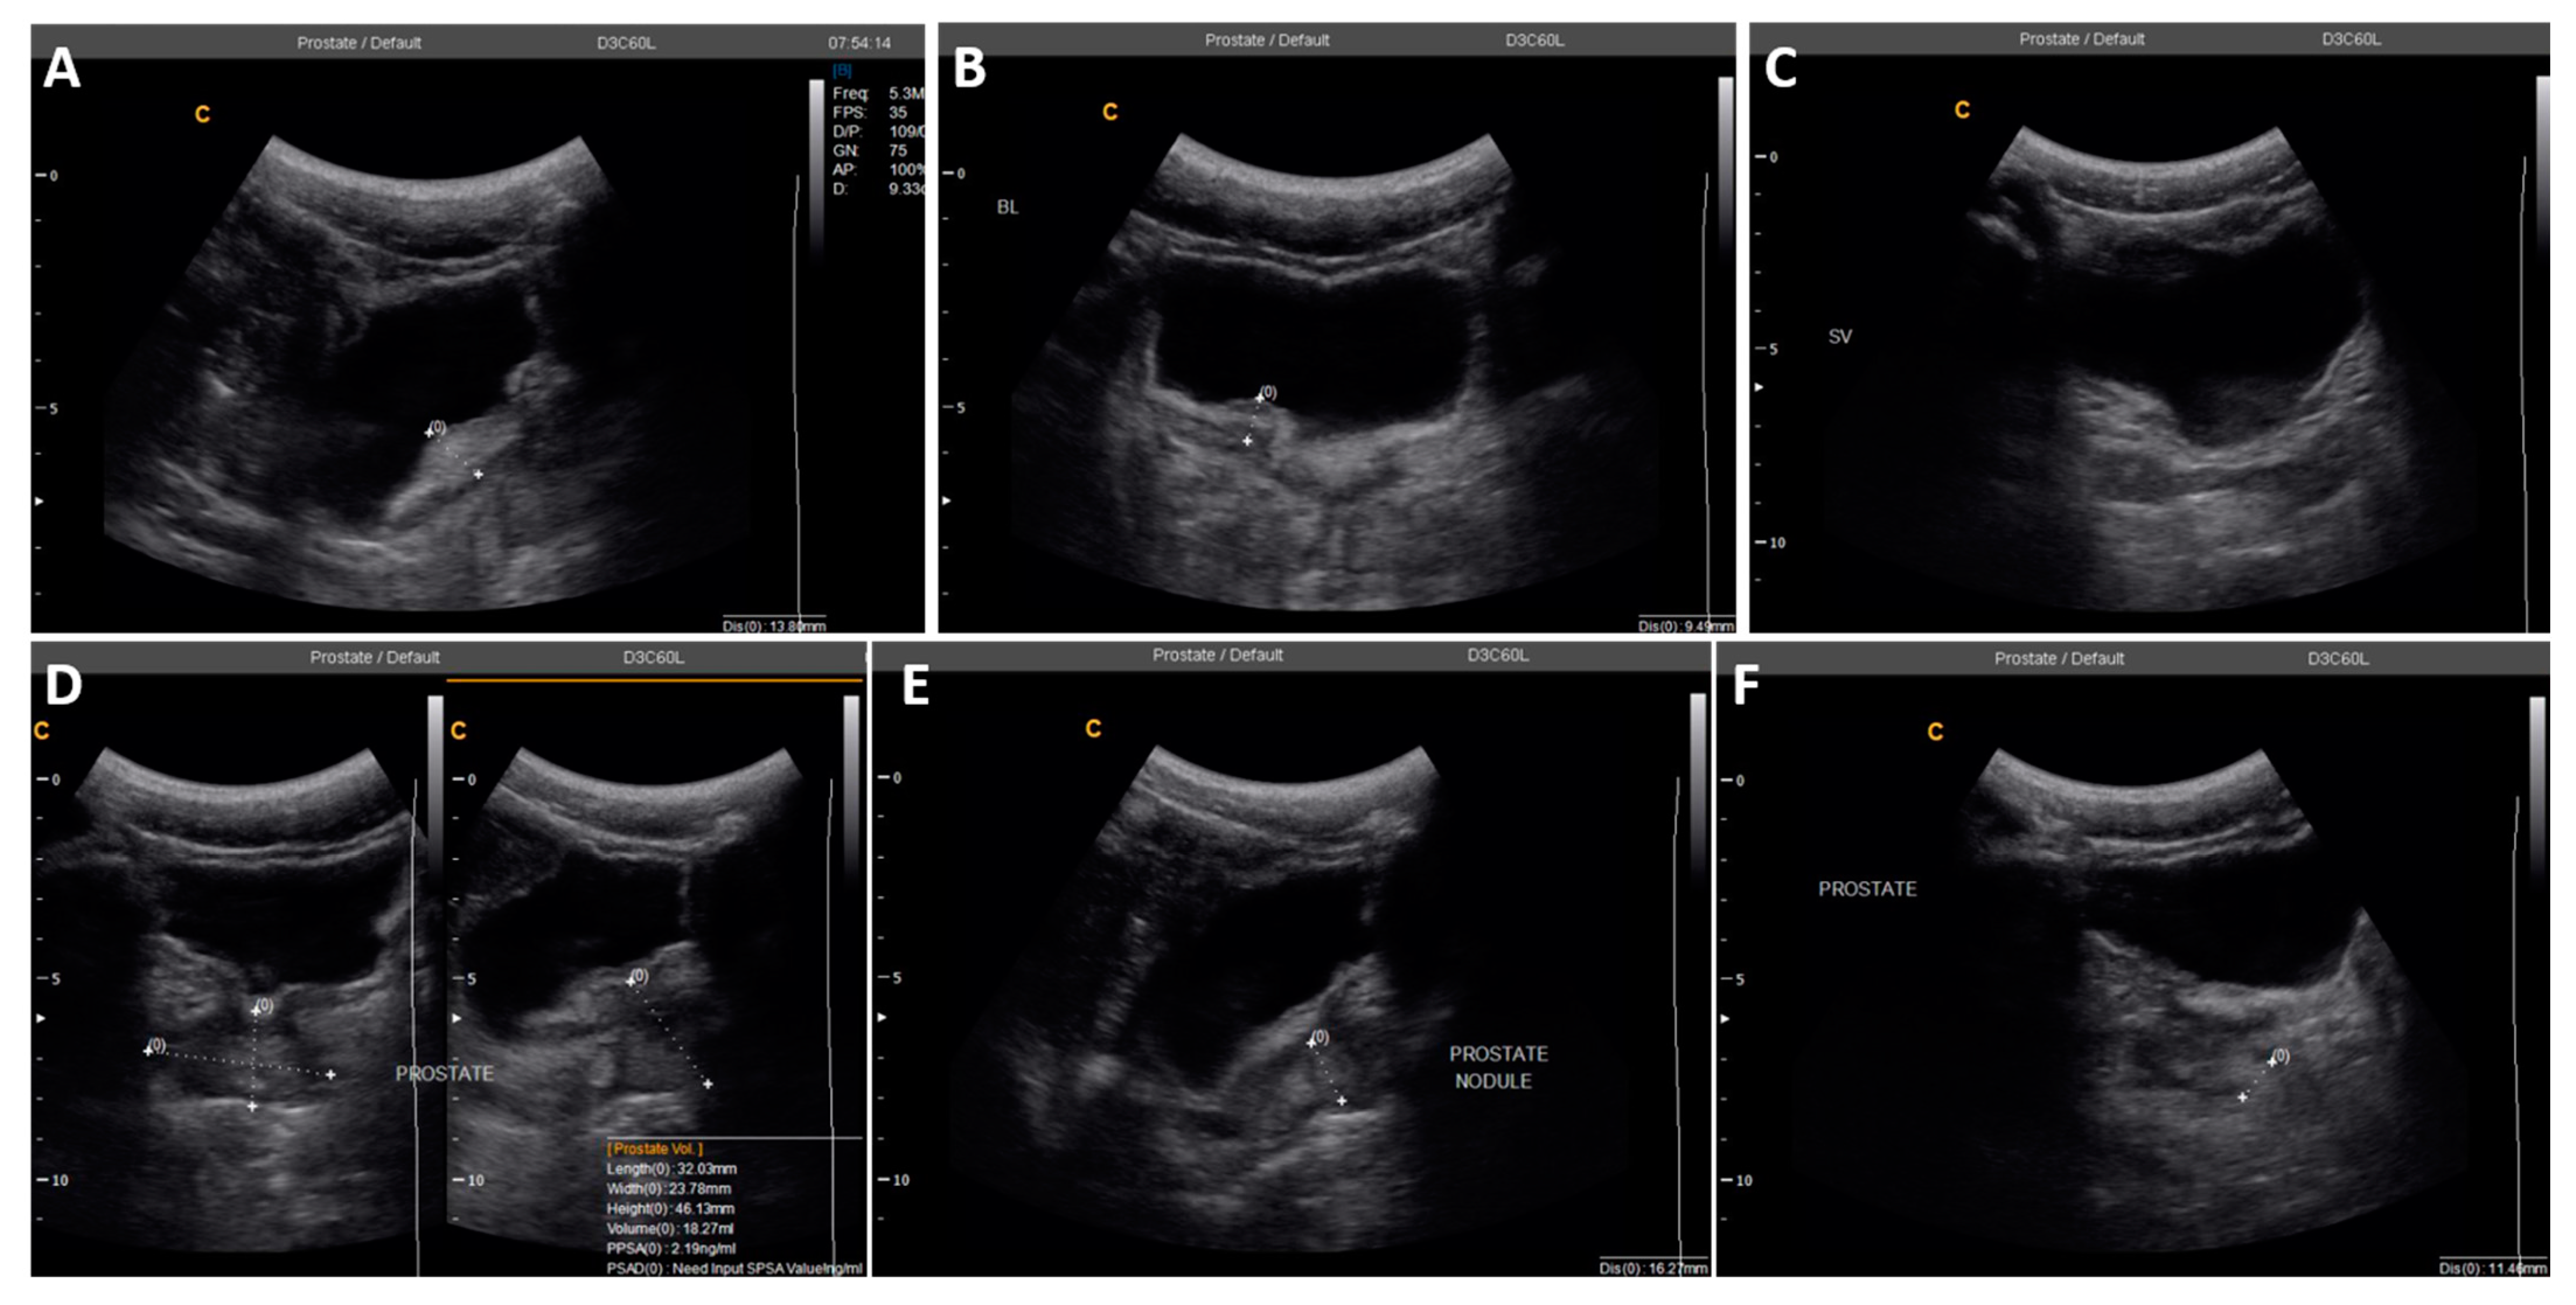

| 2 | 22 | 0 | 0 | 25.4 | Irregular bladder wall with severe focal thickness, irregular prostate with hyperechoic nodule (Figure 3) |

| 3 | 49 | 1 | 6 | N/D # | Left testicular nodule and mild bilateral hydroceles |

| 4 | 69 | 0 | N/A ǂ | N/A ǂ | Severely enlarged prostate (volume = 61.3 mL) and right epididymis, with bilateral hydrocele |